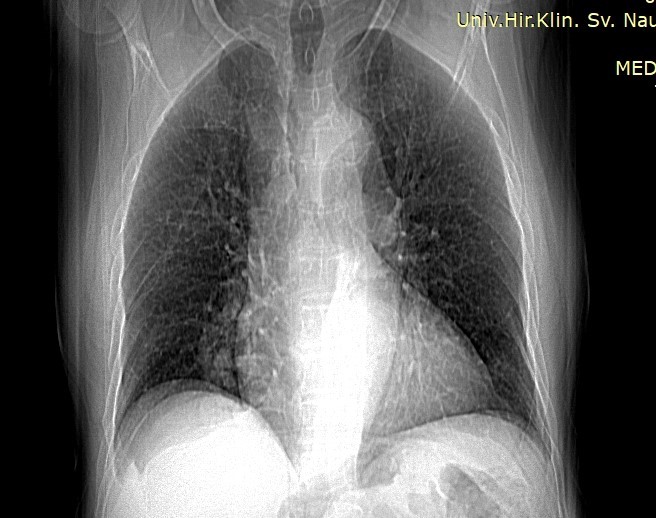

We present a case of 73-years-old patient who underwent MDCT of the lungs due to visualization of a lobulated shadow right paracardial on preoperative chest radiography. The patient did not exhibit signs of dyspnea, bleeding, or any occlusive changes of the blood vessels. Laboratory analyses were within normal limits.

On the chest radiograph, a shadow was visualized in the paracardial right area with lobulated contours. The surrounding parenchyma appeared normal, and the hila were unremarkable.

Image 1. Chest radiograph (PA and lateral view) showing a lobulated shadow in the right paracardial area.